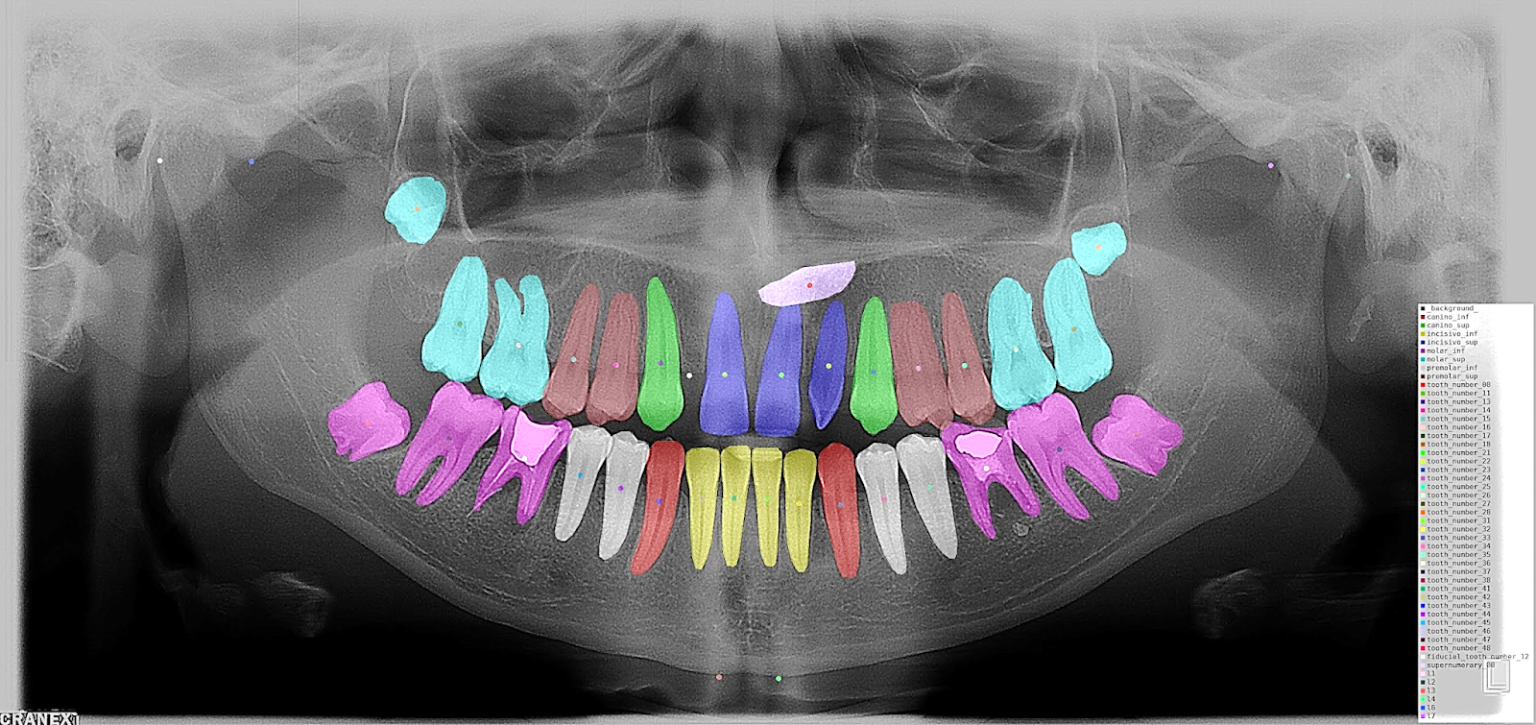

IA en Odontología

Inteligencia Artificial en Odontología

Desarrollo de algoritmos de IA para el diagnóstico temprano de patologías dentales mediante análisis de imágenes radiográficas.

Ecodoc Dental Ganador Fondo Semilla 2024